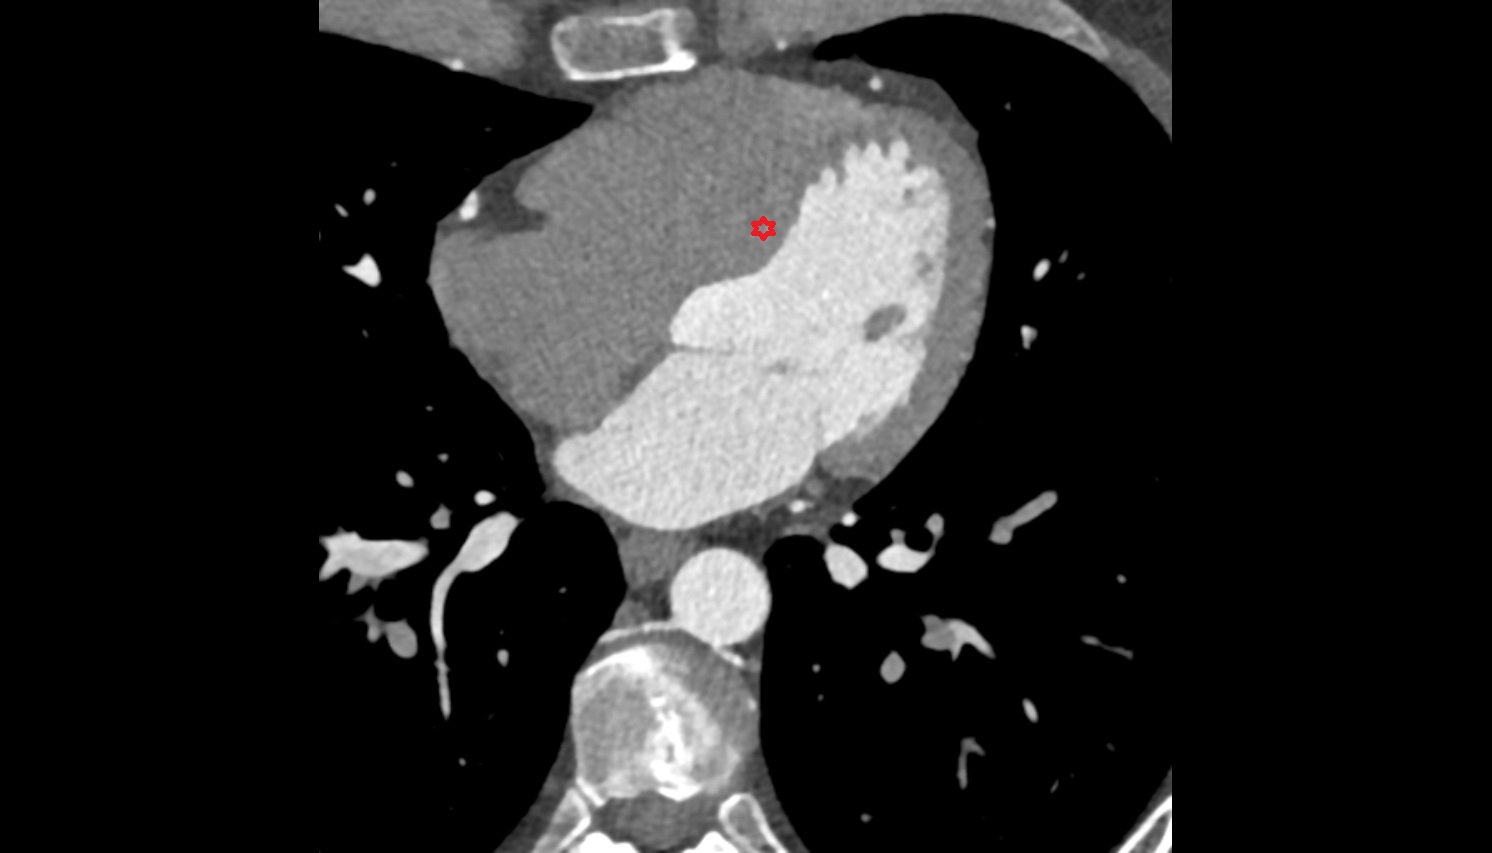

- Pericardium

- Heart

- Left ventricle

- Right atrium

- Left atrium

- Right ventricle

- Interventricular Septum

- Myocardium